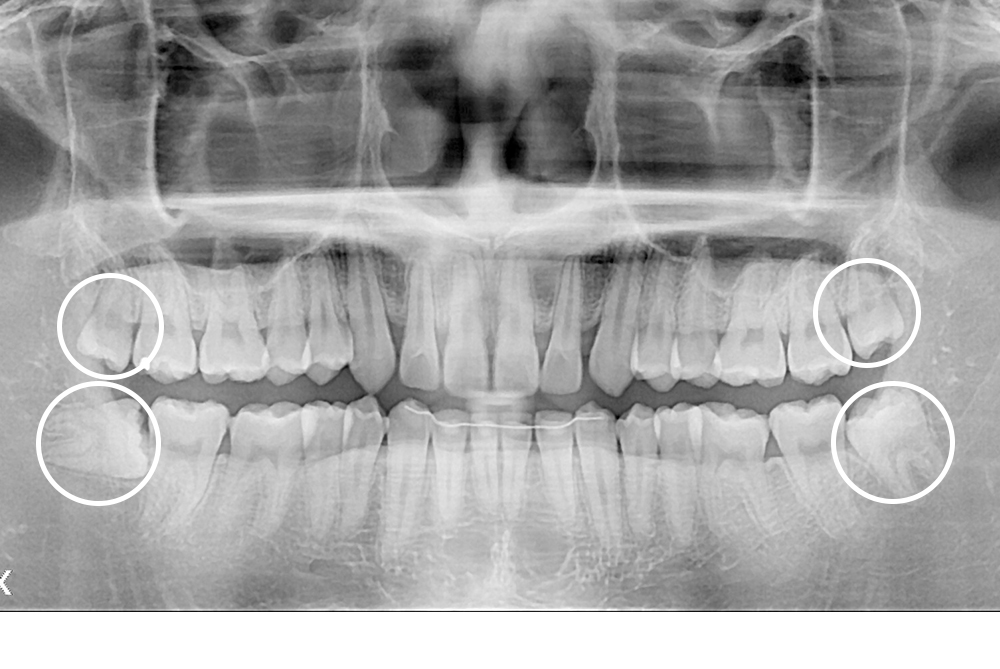

[사랑니] 매복 사랑니 발치

치료후 : 2017-09-26

세종치과는 구강악안면외과학 박사이신 원장님이 발치하는 치과입니다.